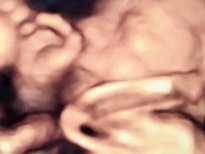

Anne karnındaki bebeklerin gülümseten pozları

Anne adayları için en heyecanlı an olan bebeğin anne karnında ilk görüntüleri, görenlere 'Adeta poz vermiş' dedirtiyor. 16'ncı haftadan itibaren yüzü şekillenmeye ve gelişmeye başlayan bebeklerin ultrasonla çekilen fotoğrafları arasında kaşları çatık, gülen, eliyle yüzünü kapatan, burnuyla oynayan, parmağını emen, elini çenesine dayayan bebekler olduğu gibi kendini göstermeyen bebekler de var.